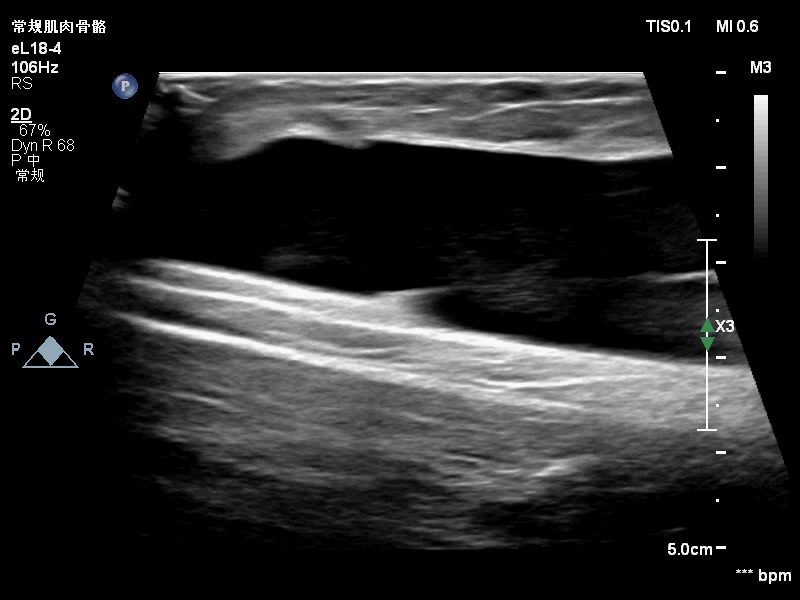

范特西_ 推荐男孩,12y,骑自行车过程中摔倒,右大腿内侧撞到了路边护栏,已有4-5天,今因大腿内侧肿胀就诊,声像图如下:

感觉是脂肪层和深方的深筋膜分离后积血。?所示应该是深筋膜吧。

大家考虑脱套伤吗?在报告中应怎么诊断?望各位老师指点。